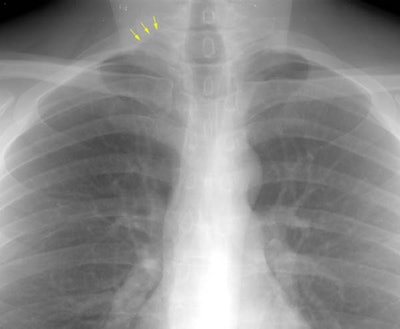

Sarcoid Stage 1:

The patient is an active duty troop who presented to the emergency department because of URI complaints. The chest radiograph demonstrated right paratracheal and bilateral hilar adenopathy (the "1-2-3 sign" of sarcoid). Transbronchial biopsy confirmed the diagnosis of sarcoid. (Click here to view the lateral exam which demonstrated increased density over the hila)